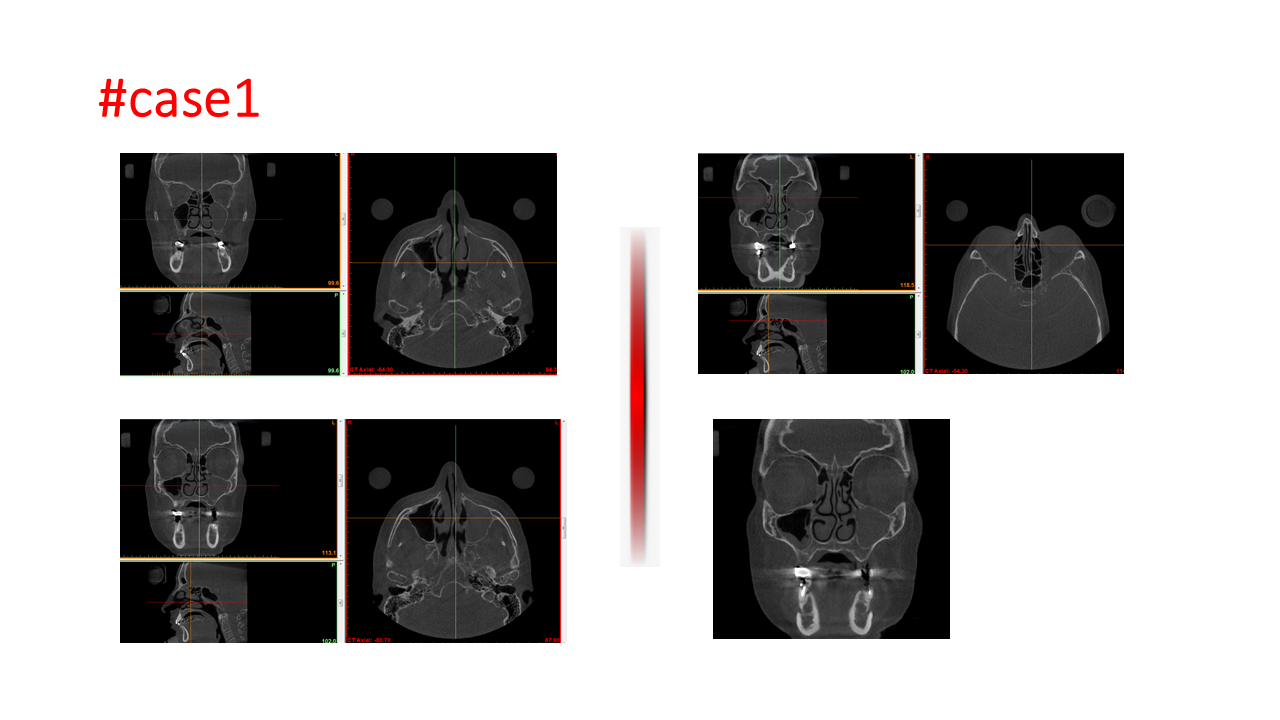

FESS Case Review and Radiologic Analysis (30.09.2016)

Case-based presentation focused on pre- and postoperative imaging in functional endoscopic sinus surgery (FESS). Includes anatomical landmarks, surgical variations, sinus pathology, and technique evaluation. Delivered by Dr. Levon Galstyan at AAOMFS.